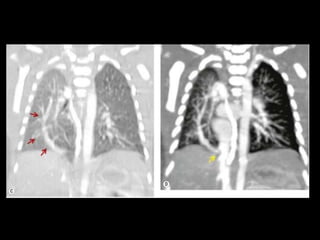

MAV complexa

Malformação arteriovenosa(MAV) MAV congênitas: fístulas vasculares com comunicação entre a artéria e a veia pulmonar(95%) ou de uma artéria sistêmica e a veia pulmonar com by-pass do leito capilar; Cerca de 50% das MAVs estão associadas com Síndrome de Rendu-Osler-Weber(teleangiectasia hemorrágica hereditária); O diagnóstico costuma ser bem direto pela TC;

Malformação arteriovenosa(MAV) TC:o aspecto típico é de uma massa regular, lobulada, redonda ou oval, ou até o de uma formação serpenginosa, com menos de 1 cm a vários cm de tamanho, associada a uma artéria nutriz visivelmente aumentada e uma veia de drenagem alargada; Uma ANGIO-TC geralmente faz o diagnóstico; Tratamento pode ser realizado com terapia embólica.